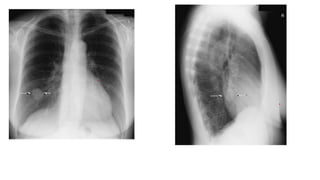

Lateral view-standing

• A supplementary lateral projection may be

useful in certain clinical circumstances for

localizing the position of a lesion and

demonstrating anterior mediastinal masses

not shown on the postero-anterior

projection.

• Position of patient and cassette

• The patient is turned to bring the side under

investigation in contact with the cassette.

• • The median sagittal plane is adjusted

parallel to the cassette. • The arms are

folded over the head or raised above the

head to rest on a horizontal bar.

• • The mid-axillary line is coincident with the

middle of the film, and the cassette is

adjusted to include the apices and the lower

lobes to the level of the first lumbar

vertebra.

Lateral view-standing • Asupplementary lateral projection may be useful in certain clinical circumstances for localizing the position of a lesion and demonstrating anterior mediastinal masses not shown on the postero-anterior projection. • Position of patient and cassette • The patient is turned to bring the side under investigation in contact with the cassette. • • The median sagittal plane is adjusted parallel to the cassette. • The arms are folded over the head or raised above the head to rest on a horizontal bar. • • The mid-axillary line is coincident with the middle of the film, and the cassette is adjusted to include the apices and the lower lobes to the level of the first lumbar vertebra.